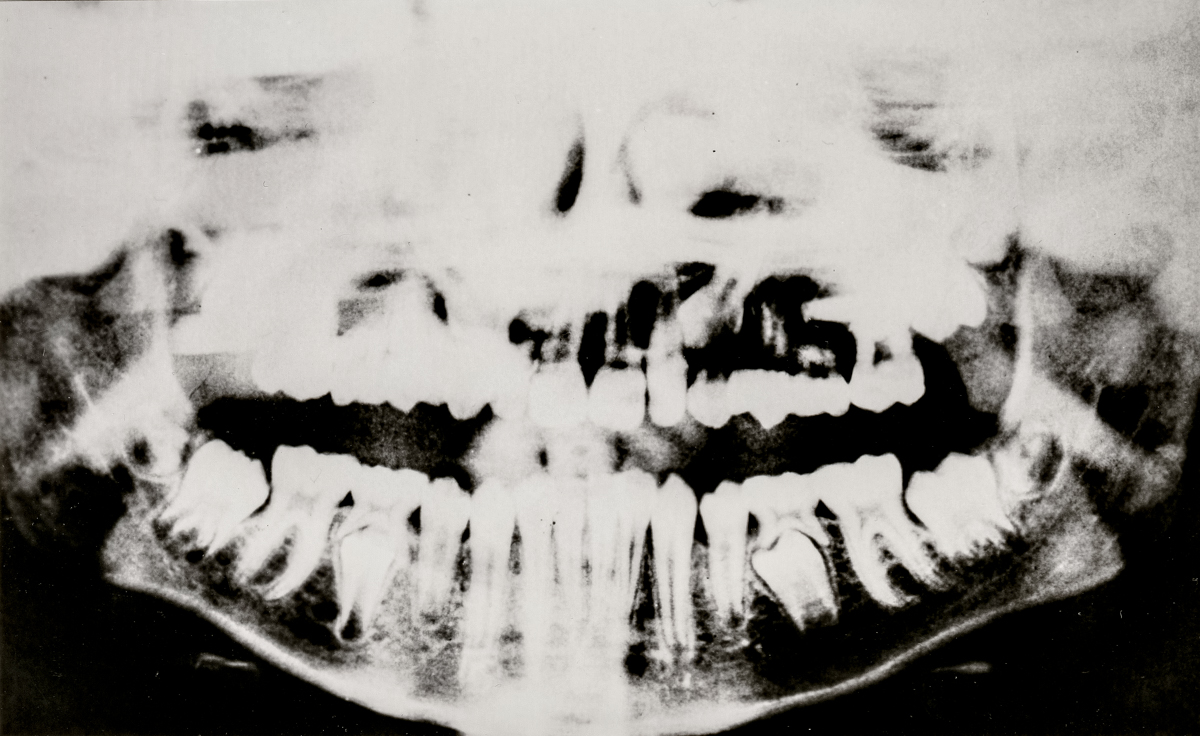

SURFACES SENSIBLES — À la frontière de l'autoportrait, "Surfaces sensibles" retranscrit une partie de ma réalité et brouille les limites entre l'intime anatomique et l'émotionnel.

La science produit les images les plus concrètes et les plus neutres pour illustrer les affects. Pourtant, par leur froideur et leur distance, elles sont les moins aptes à témoigner des émotions. Chaque radiographie, scanner, IRM correspond à une douleur ou à un mal-être spécifique.

Depuis peu, ces images ne sont plus seulement des réminiscences de douleurs passées, mais également des matériaux bruts inspirants pour ma pratique photographique. À partir des radios originelles, j'ai utilisé plusieurs techniques telles que la superposition et le tirage argentique dans le but de me rapprocher d'une perception alternative de ce corps irradié.